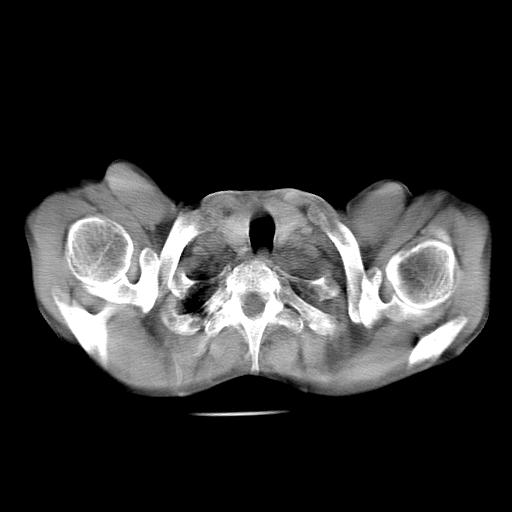

标题: CT27010:男 70岁 左胸廓塌陷,肺TB [打印本页]

男  70岁,发烧咳嗽4天。盗汗,消瘦。无痰中带血丝,以前有肺tb病史,ct见,双肺tb,左侧胸廓塌陷,左胸膜肥厚粘连。纵隔移位,右侧胸腔积液,大家说说那个心影前左肺舌叶除了肺大炮还有炎症还是干酪性肺炎?有占位吗?我看纵隔淋巴结也大。

是胃,纵膈未见明显肿大淋巴结。